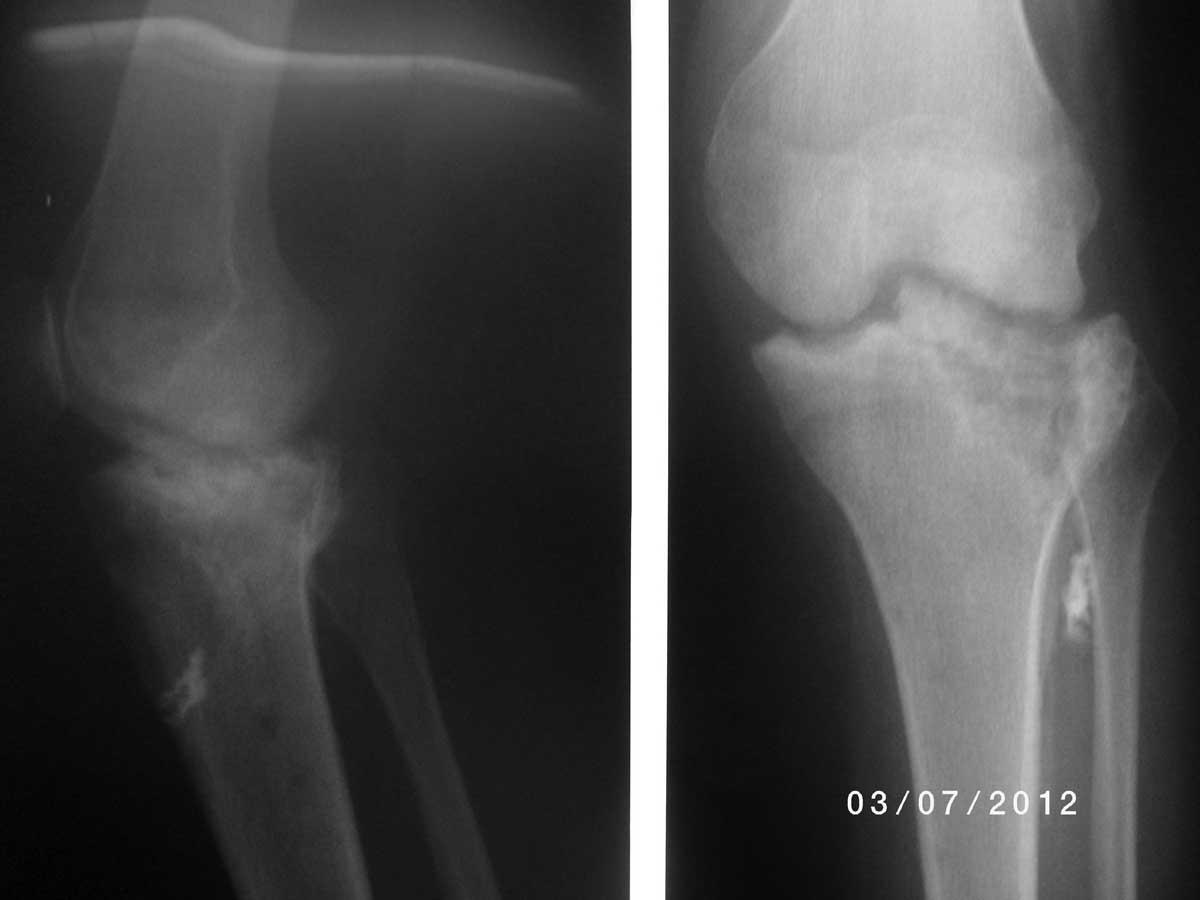

Пациентка Б. 1965 г.р., травма от августа 2011г. закрытый перелом медиального мыщелка большеберцовой кости. Остеосинтез пластиной.

Осложнился нагноением раны. В декабре 2011г. пластина удалена. Неоднократные ревизии. В июле 2012г. появился свищ с гнойным отделяемым. Снимки на данный момент. Планирую санацию, некрсеквестрэктомию, аппаратную фиксацию, проточно-промывное дренирование (7-10 дней), протезирование через 1 год. Коллеги, посоветуйте по тактике лечения. Спасибо. (Старался коротко)